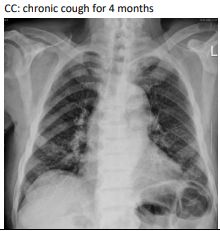

1.